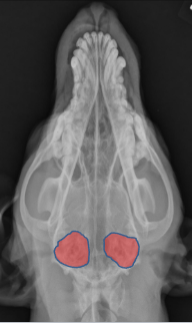

Tympanic Bulla